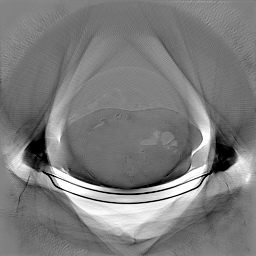

The experimental results on clinical head data are shown in Fig. 4. The reference images were reconstructed using the fast iterative shrinkage-thresholding algorithm (FISTA) with total variation regularization from non-truncated projection data. In the WCE reconstructions (Fig. 4(b)), severe truncation prevents accurate recovery of anatomical structures outside the FOV. Despite being trained solely on simulated data with a domain gap, all deep learning models can restore a substantial portion of the missing anatomy. Among them, the diffusion-based methods recover soft-tissue boundaries more faithfully than the conventional deep learning approach FBPConvNet, highlighting their stronger image generation capability. However, cDDPM reconstructions exhibit more noticeable noise than those from other methods, consistent with the simulated data results. The patchDiffusion model introduces artifacts within the FOV, likely due to its patch-wise processing strategy. While I2SB shares the same limitations as other diffusion models in perfectly restoring soft-tissue detail, it produces fewer residual noise patterns and fewer artifacts within the FOV boundaries. Overall, Fig. 4 demonstrates the strong efficacy of I2SB in reconstructing real CBCT data.